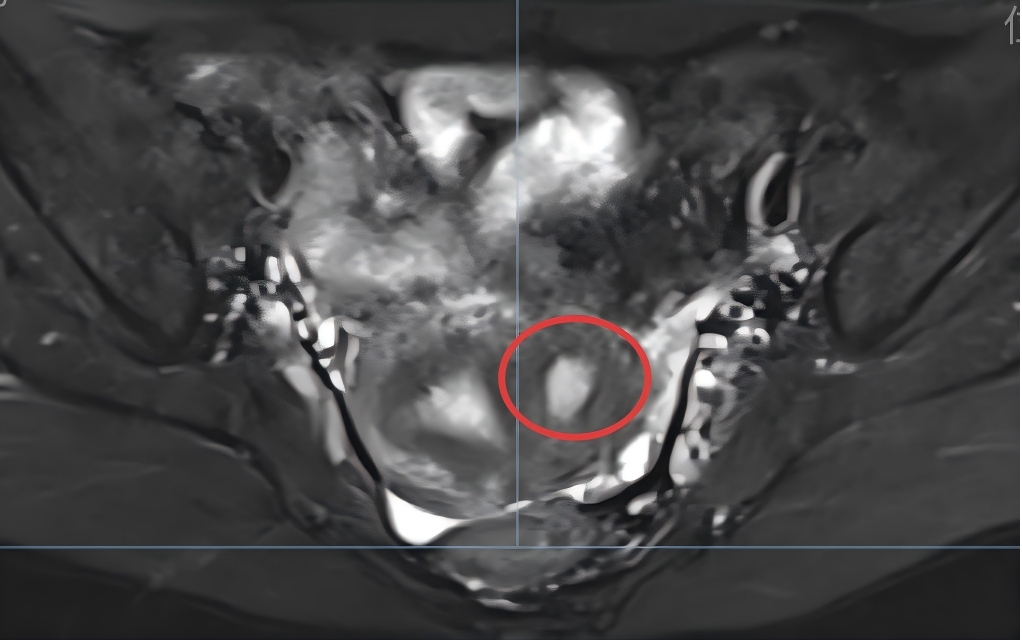

在南通一院妇科,诊疗团队并未止步于常规检查。医生细致追溯小月的病史,结合精准超声影像检查,并凭借深厚的临床经验层层排查,最终确诊其患有子宫附腔——一种因苗勒管发育异常导致的罕见先天性子宫畸形,病灶位于子宫肌壁间,是一个与正常宫腔不相通、内衬子宫内膜的“封闭小腔隙”。

据郑艳莉主任介绍,子宫附腔是罕见的梗阻性生殖道畸形,患者多为未生育的年轻女性,常表现为严重痛经、经期延长或慢性盆腔痛,部分患者早期可能无明显症状,生育后或年龄增长才逐渐出现不适。诊断上,三维超声是经济有效的初筛手段,磁共振成像(MRI)则是确诊的“金标准”;治疗需根据症状轻重选择定期观察或手术切除,腹腔镜手术因创伤小、恢复快,是目前推荐的主要术式。